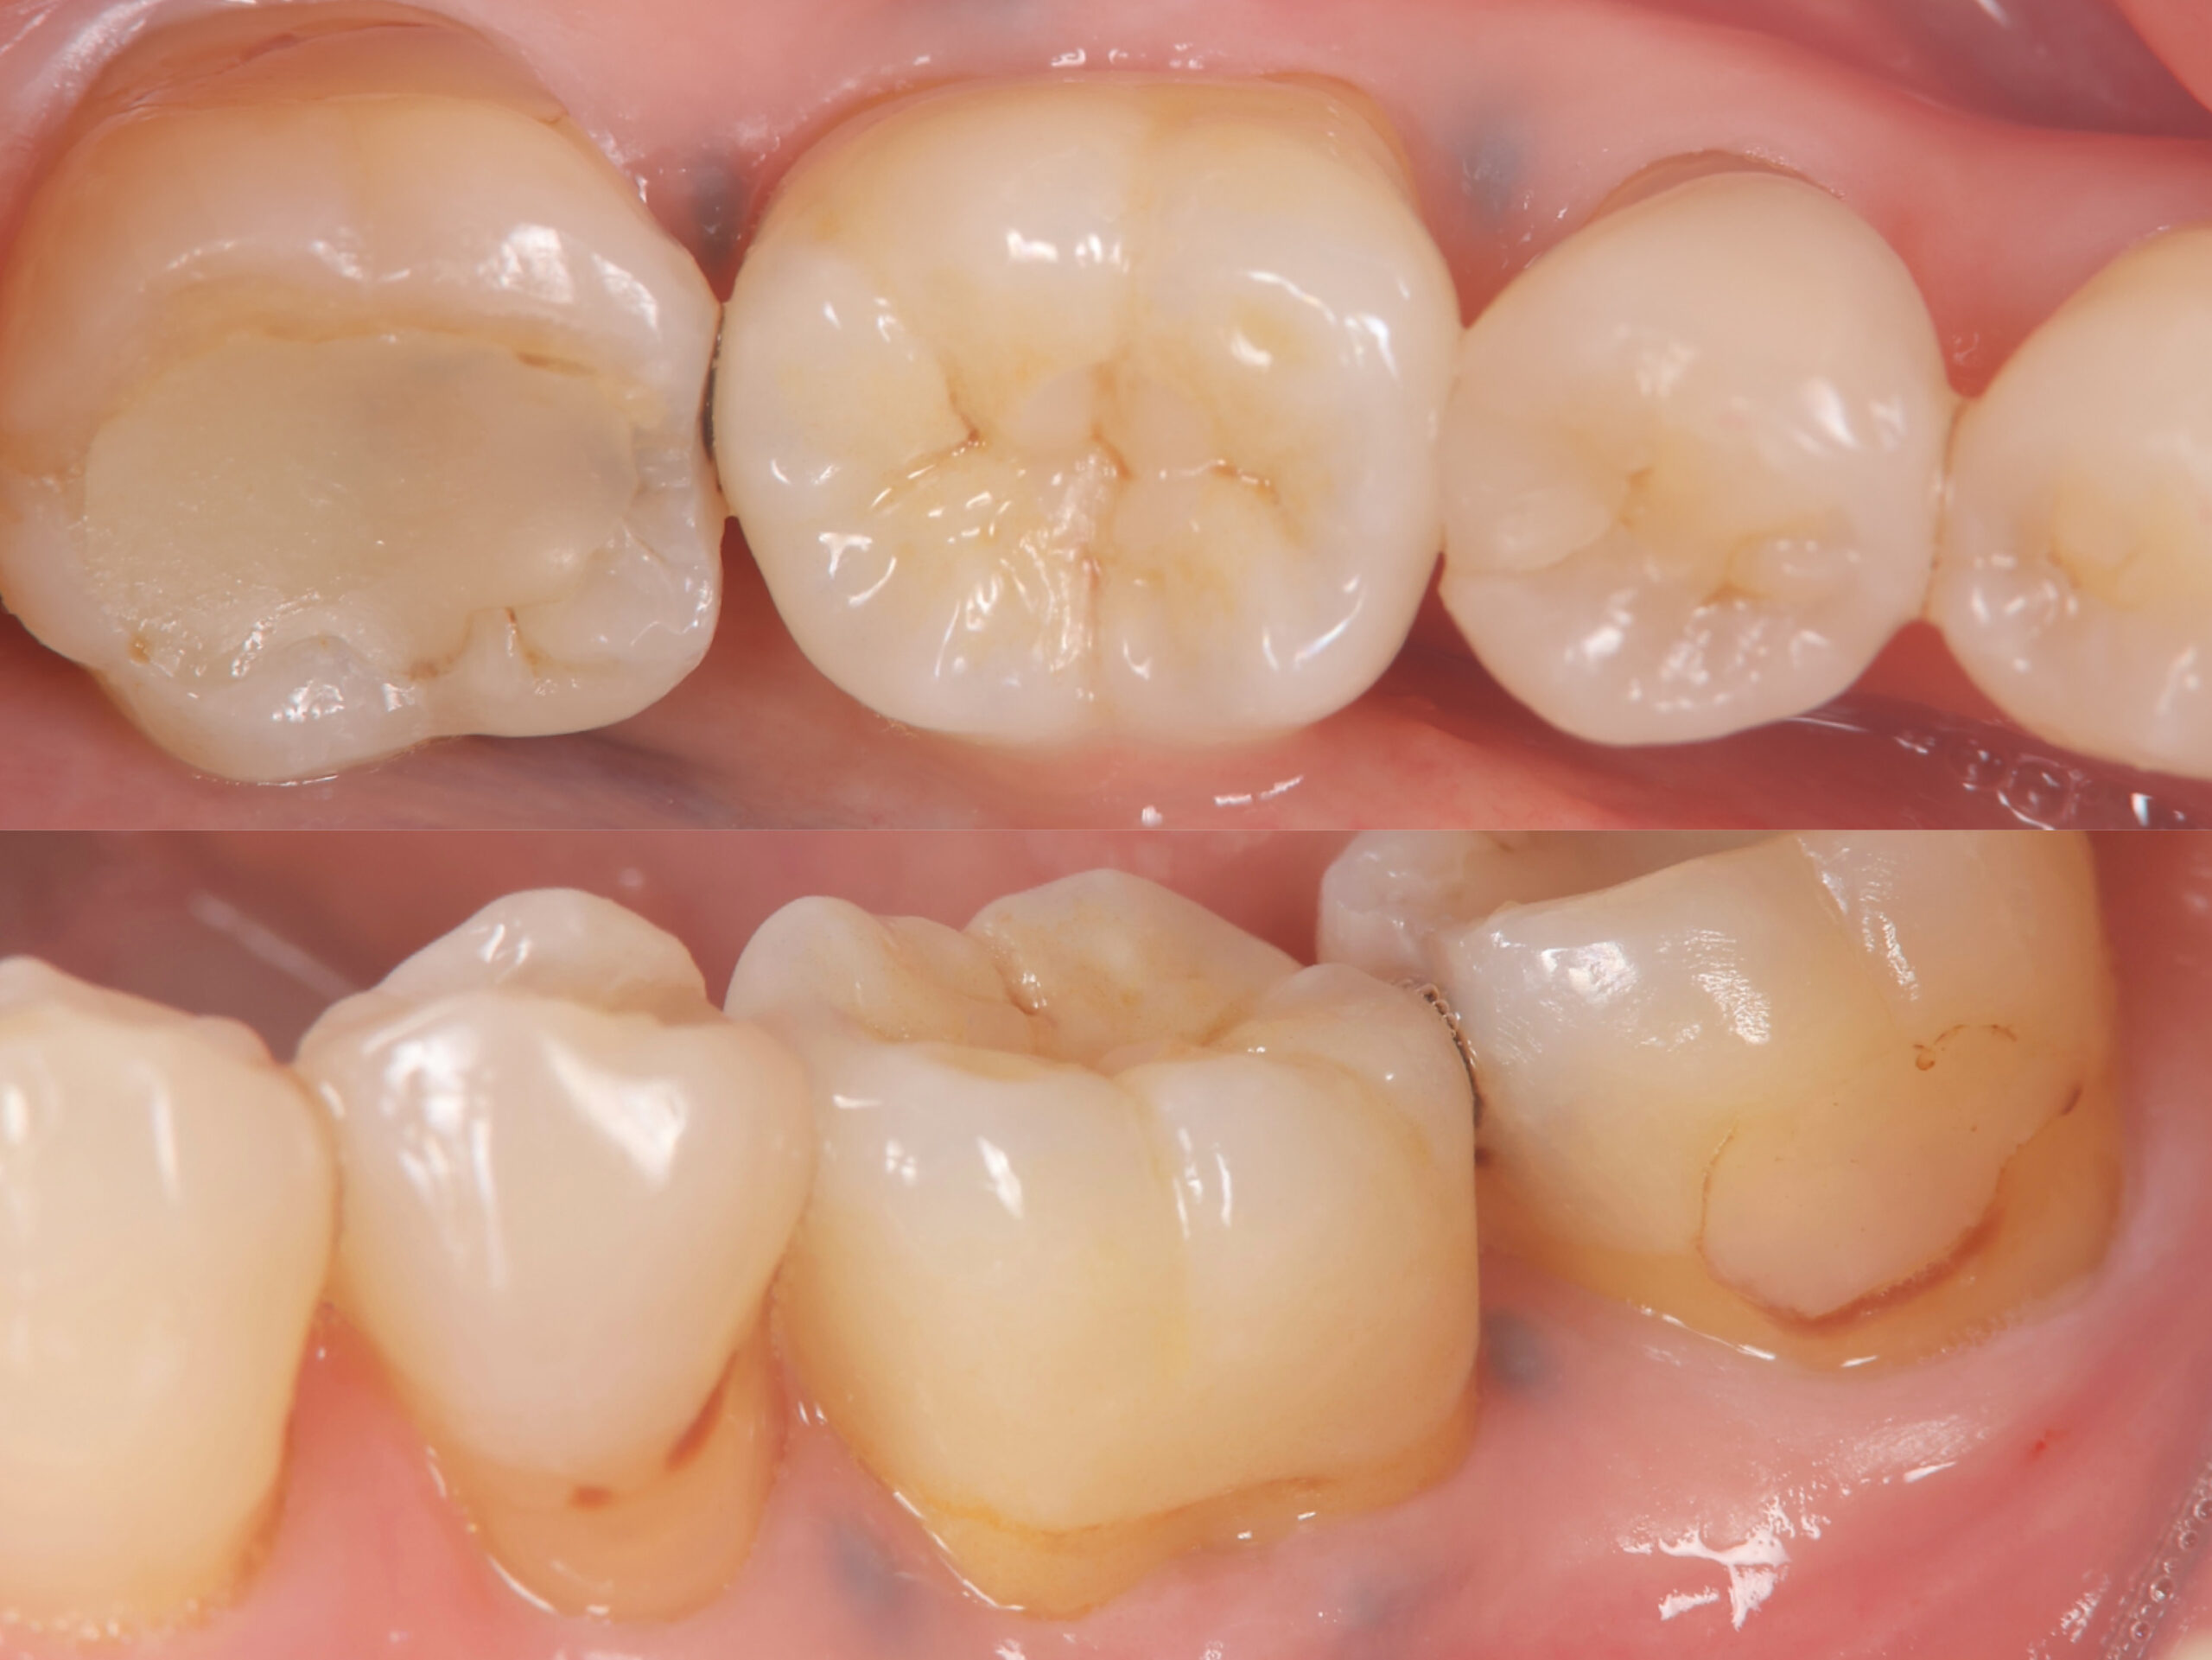

この画像はインプラント治療後の画像です。どこにインプラントが入っているか、お分かりでしょうか?これは第一大臼歯(後ろから2番目)を治療させていただいた際のものです。先ほどお伝えした、耐久性・清掃性・審美性をクリアした私の自信作です✨